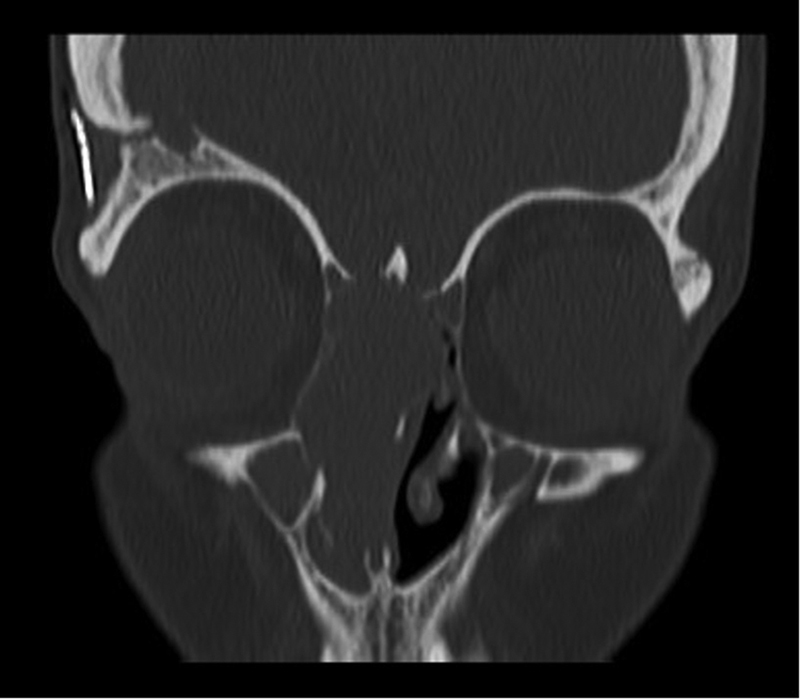

背景 放射治疗是治疗脑肿瘤的主要方法,但延迟并发症包括继发性恶性肿瘤,可能在治疗结束后数月至数年发生。方法 我们回顾了一名 41 岁女性的病历,她因复发性星形细胞瘤接受了 60 Gy 的放射治疗,6 年后又患上了局部晚期鼻窦畸胎肉瘤。我们检索了MEDLINE、Embase和Web of Science,对曾因脑肿瘤接受过头颅照射的患者中经活检证实的鼻窦恶性肿瘤进行了范围界定。结果 据我们所知,这是首例因脑瘤接受颅内照射后出现鼻窦畸胎肉瘤的患者报告。我们对 1907 项研究进行了范围审查,发现了 14 例类似的继发性鼻窦恶性肿瘤病例。原发癌诊断的中位年龄为 39.5 岁(标准差 [SD]:21.9),中位放射剂量为 54 Gy(标准差:20.3)。原发性癌症与继发性鼻窦癌之间的中位潜伏期为 9.5 年(标准差:5.8)。嗅神经母细胞瘤是最常见的鼻窦癌(4 例)。50%的患者在1.5年内死于鼻窦癌。结论 因治疗原发性脑肿瘤而接受鼻窦部位放射线照射(包括低剂量或散射辐射)的患者可能会面临日后罹患继发性鼻窦恶性肿瘤的风险。监测高危患者的医生必须对可能提示鼻窦恶性肿瘤的症状保持警惕,监测工作应包括对整个照射区域进行放射学检查,并仔细观察是否存在继发性恶性肿瘤。

Background  Radiation therapy is a mainstay of treatment for brain tumors, but delayed complications include secondary malignancy which may occur months to years after treatment completion. Methods  We reviewed the medical records of a 41-year-old female treated with 60 Gy of radiation for a recurrent astrocytoma, who 6 years later developed a locally advanced sinonasal teratocarcinosarcoma. We searched MEDLINE, Embase, and Web of Science to conduct a scoping review of biopsy-proven sinonasal malignancy in patients who previously received cranial irradiation for a brain tumor. Results  To our knowledge, this is the first report of a patient to present with a sinonasal teratocarcinosarcoma after receiving irradiation for a brain tumor. Our scoping review of 1,907 studies produced 14 similar cases of secondary sinonasal malignancy. Median age of primary cancer diagnosis was 39.5 years old (standard deviation [SD]: 21.9), and median radiation dose was 54 Gy (SD: 20.3). Median latency time between the primary cancer and secondary sinonasal cancer was 9.5 years (SD: 5.8). Olfactory neuroblastoma was the most common sinonasal cancer ( n  = 4). Fifty percent of patients died from their sinonasal cancer within 1.5 years. Conclusion  Patients who receive radiation exposure to the sinonasal region for treatment of a primary brain tumor, including low doses or scatter radiation, may be at risk of a secondary sinonasal malignancy later in life. Physicians who monitor at-risk patients must be vigilant of symptoms which may suggest sinonasal malignancy, and surveillance should include radiographic review with careful monitoring for a secondary malignancy throughout the entire irradiated field.